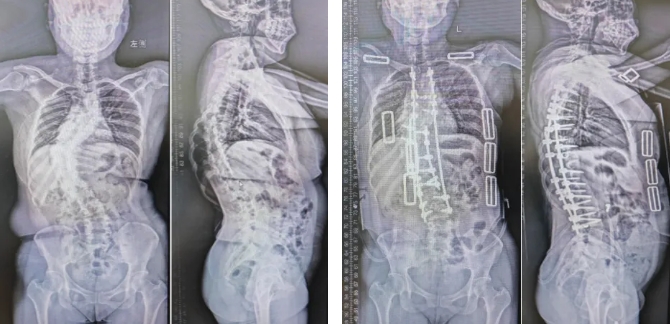

3.面对数量庞大的成人退变性脊柱侧弯、或因强直性脊柱炎、陈旧性骨折等疾患导致的脊柱畸形、脊髓慢性损伤患者,通过截骨矫形+内固定技术,重建脊柱-骨盆平衡,帮助患者恢复脊髓功能,显著改善患者生活质量。

33岁的患者徐女士,幼年时先天性多发性半椎体畸形,因身处偏远地区,未及时手术,脊柱侧弯度数逐年加重,腰背部进行性疼痛,内脏受压,并导致肺功能明显受损,经截骨矫形手术后患者畸形明显改善,胸腔有效容积扩大,患者腰背痛减轻,活动功能明显改善。